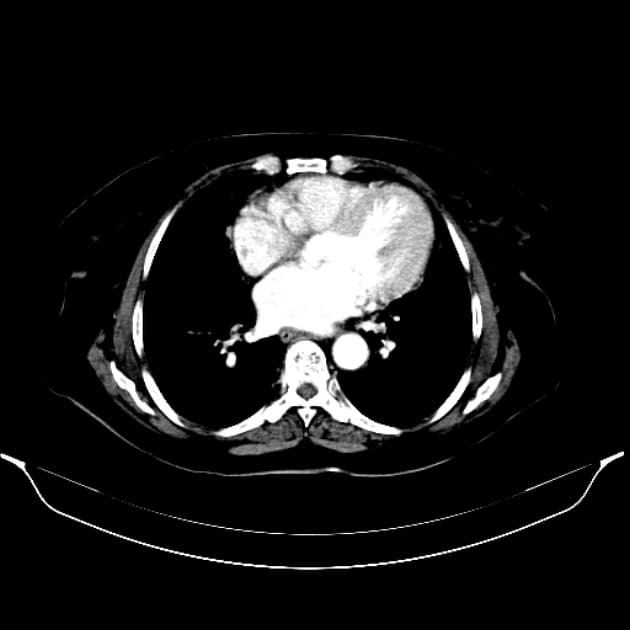

Axial T1 C+ fat sat

- Nhiều tổn thương khối mờ tăng quang khuếch tán khắp gan trên thì tĩnh mạch cửa.

- Các khối này tăng tín hiệu nhẹ trên T1 và T2, ranh giới không rõ trên hình ảnh thông thường sau tiêm thuốc cản quang, nhưng hiện rõ là nhiều tổn thương giảm tín hiệu trên chụp chậm với Primovist (chỉ điểm không có tế bào gan, do đó loại trừ u tăng sản khu trú - FNH).

Nhiều tổn thương khối tăng quang, không có tế bào gan dựa trên hình ảnh chụp chậm sau tiêm thuốc cản quang. Chẩn đoán phân biệt bao gồm: bệnh di căn, ung thư biểu mô tế bào gan đa ổ (HCC) và u tuyến gan. Bệnh nhân đã được sinh thiết 3 tổn thương riêng biệt, kết quả đều cho thấy u tuyến gan (adenoma). Vì có trên 10 tổn thương, nên được gọi là tăng sản tuyến gan (adenomatosis). Tình trạng này có thể liên quan đến việc sử dụng thuốc tránh thai uống (OCP). Không thấy hình ảnh xuất huyết cấp, một biến chứng có thể xảy ra trong bệnh lý này.

Tăng sản tuyến gan (Hepatic adenomatosis)